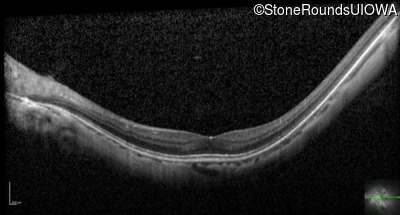

Optical Coherence Tomography - Left - 20/50 -2

Exemplar / OCT Stack